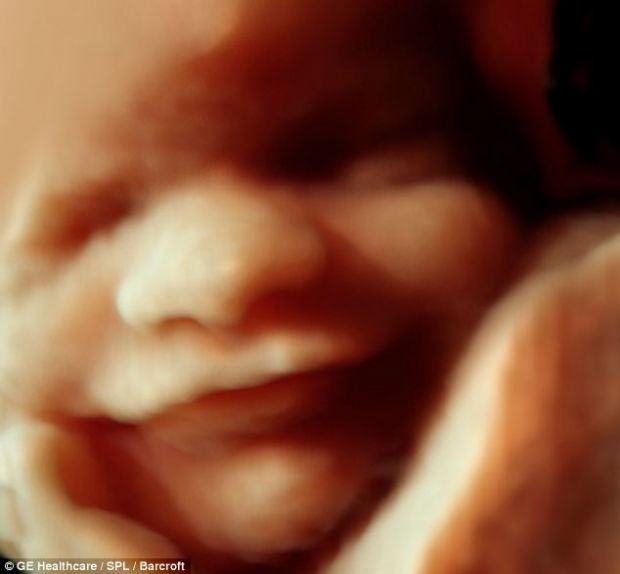

16 – 18 haftalık fetus

Anne karnında 18 haftalık bebeğin görünümü.jpg